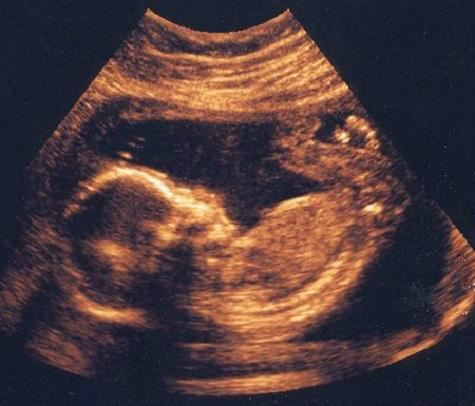

A mãe nem a equipe médica esperavam quadrigêmeas. Um ultrassom foi feito apenas no início da gestação e o exame apontou gêmeos. O acontecido é considerado normal pelo fato de o ultrassom ter sido feito no começo da gravidez.